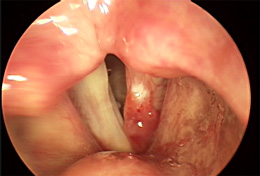

Early symptoms of throat cancer include hoarseness of the voice, difficulty in normal voice production during speech, changes in the voice, sore throat, continuous dry cough, perceivable pain while swallowing saliva, liquid and solid food, pain in the ear, difficulty breathing, a small swelling or a lump in the throat or neck region, and unexplained weight loss. In some types of throat cancer, such as cancer of the larynx, visible early cancer symptoms can be observed during a medical examination. This includes a typical visible red patch with an irregular surface on the voice box.

A Visible Early Cancer Symptom of the Larynx